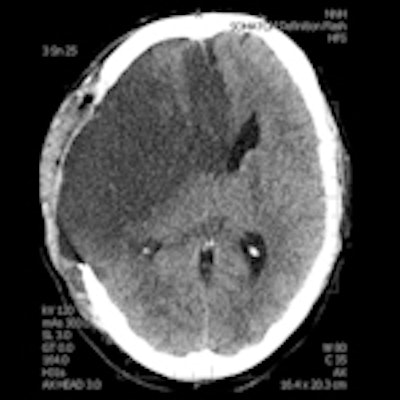

A 28-year-old male with a history of aortic valve replacement and poor compliance with anticoagulative medication, presented with sudden left-sided hemiplegia. No penumbra was apparent on perfusion CT, as shown in left figure (CBF) and middle figure (CBV). Standard CT image (right figure) two days following decompressive craniectomy shows significant mass effect with dislocation of midline structures. Images courtesy of Dr. Josef Vymazel.When ultrafast CT scanners covering almost the entire brain are used, the potential to detect ischemia and salvageable tissue is very similar to MRI. However, the major drawback of CT is the high radiation dose, while in MRI it is the more complicated and time-consuming aspect of the examination, he wrote in an article published online on 29 September by Insights into Imaging.